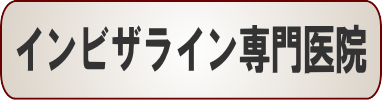

☆出っ歯矯正症例(moe様 19歳 女性)

治療解説

主訴は右上の前歯の前突感の改善です。

まずはワイヤーを使用して右上のデコボコを改善していきます。

ワイヤーの使用期間が約3か月で、マウスピースを3か月使用して歯並びを内側に傾斜して治療していきました。

トータルでの治療期間は6ヵ月で、調整料金を含めたトータルの治療費は29万円です。

歯並びの段差を改善した後に、前歯を内側に入れていくこともおおよそワイヤーで行い、期間短縮をしています。

上側だけの部分矯正では、噛み合わせは変わりませんので、見た目の改善だけの審美治療になります。

部分矯正において、ワイヤーでデコボコを改善するだけだと、矯正前よりも少しだけ前方に出てしまうため、歯の隣接面を少し削ることで前歯の前突感を改善していきます。

どこまで前歯を中に入れたいかで、隣接面を削る量は患者様の判断で決まります。

歯を削らないでデコボコを治すだけですと、デコボコのある上の左右の1番目と上の2番目の間にブラックトライアングルという隙間が残るために、ブラックトライアングルを減らすためにもその部分の隣接面を削ってブラックトライアングルを改善していきます。